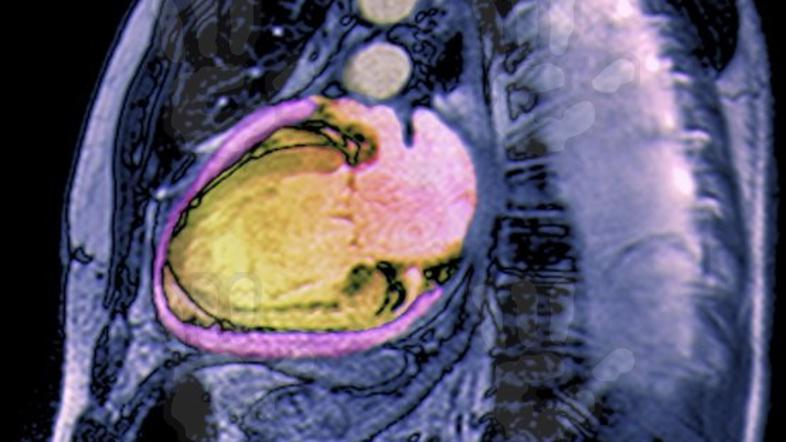

Srčno popuščanje: Bolezen z veliko trpljenja in težkim koncem

Kronično srčno popuščanje je bolezensko stanje, pri katerem okvarjeno srce ne zmore črpati dovolj krvi za potrebe drugih organov. Do srčnega popuščanja lahko pride zaradi poškodbe srčne mišice, ki jo lahko povzročijo povišan krvni tlak, bolezni srčnih zaklopk, srčni infarkt, vnetje srčne mišice ali druge bolezni srčne mišice: "Ko zdravnik predpiše zdravila, jih mora bolnik jemati redno in natančno po zdravnikovih navodilih. Zdravljenje je namreč največkrat sestavljeno in prilagojeno za vsakega posameznika," je dodal prof. dr. Bojan Vrtovec, vodja oddelka za napredovalo srčno popuščanje in transplantacije srca v ljubljanskem Univerzitetnem kliničnem centru.